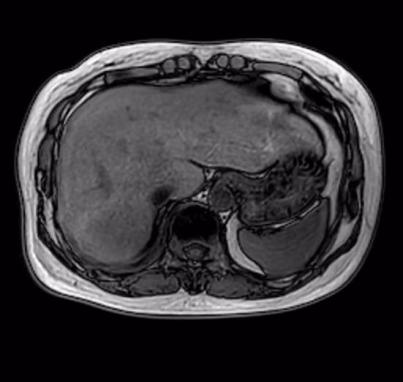

近日,哈医大肿瘤医院胸部放疗四病房尹航教授团队运用前沿空间分割放疗(SFRT)技术,成功为一名胸腺恶性肿瘤肝转移患者实施精准治疗。患者肝脏转移瘤直径由12cm显著缩小至 4.3cm,症状全面缓解,生活质量大幅提升,充分展现SFRT技术在晚期肿瘤治疗领域的突出优势和临床价值。

患者此前接受多种治疗方法,病情仍持续进展。2025年9月复查显示,肝脏转移瘤已增大至12cm,伴随明显腹胀、腹痛等症状,严重影响生活质量。面对这一复杂病情,传统治疗手段效果有限,肿瘤进展难以控制,患者一度陷入治疗困境。

治疗期间,患者肝脏转移瘤从12cm迅速缩小至7cm,体积锐减超四成。治疗后3个月复查,巨大转移瘤已缩小至4.3cm,体积缩减近三分之二,患者生化指标大幅好转,体重较治疗前显著增加,疼痛症状完全缓解,饮食、睡眠与日常活动逐步恢复正常,生活质量显著提升。

左:治疗前 中:治疗中 右:治疗后三个月